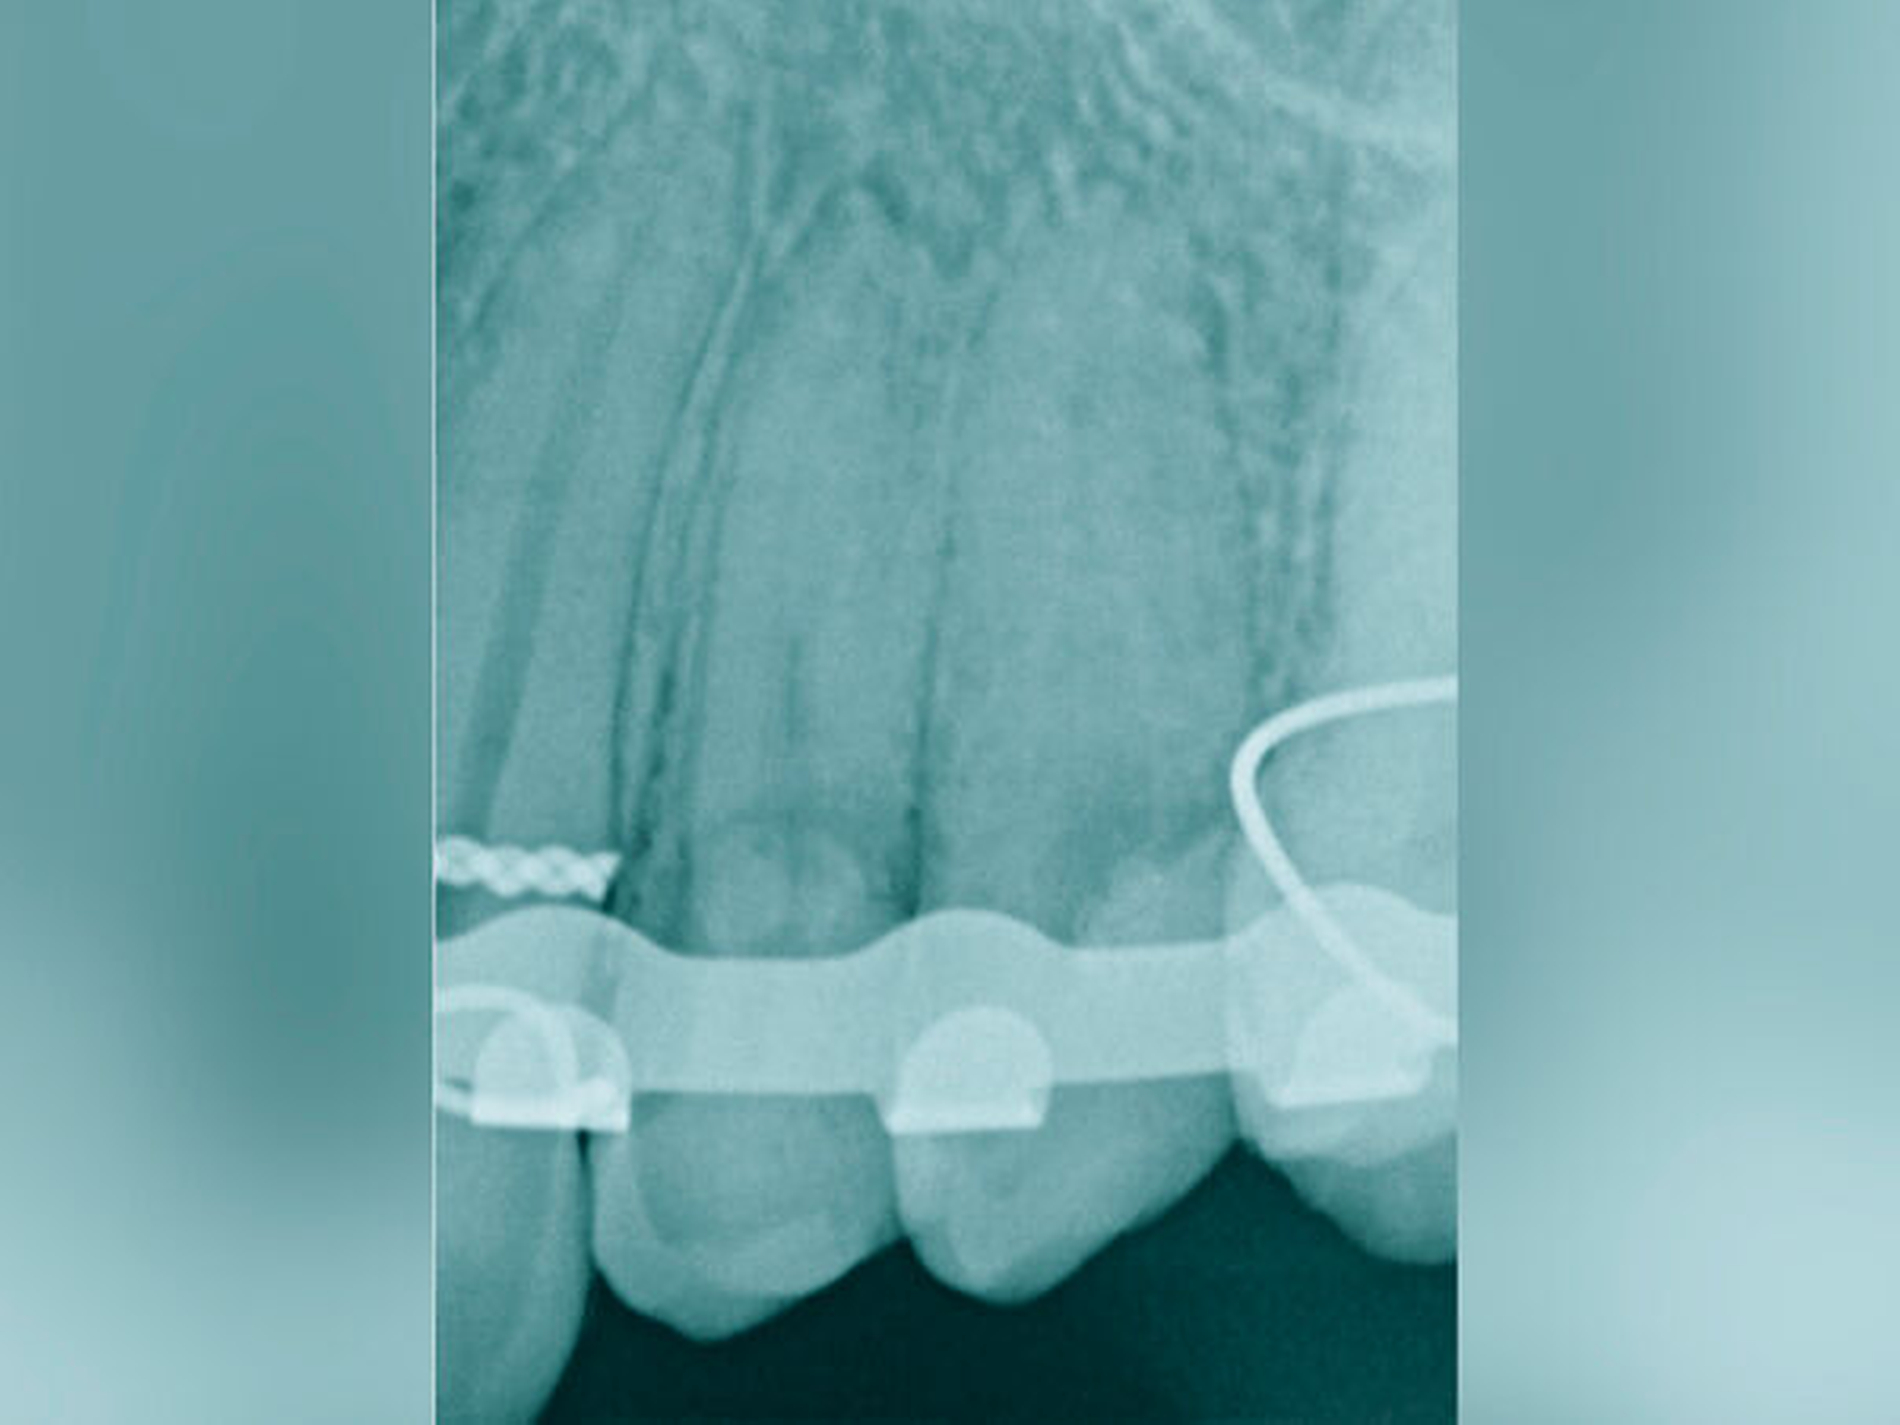

Eine weitere Möglichkeit, tief zerstörte Zähne möglichst schonend chirurgisch zu extrudieren, basiert auf axialen Zugsystemen (Abbildungen 2 bis 4). Diese erscheinen vorteilhaft bei sehr schwierigen Fällen, zum Beispiel bei Zähnen mit fehlendem Ansatzpunkt für die Zange sowie bei langen oder sehr ovalen Wurzeln. Axiale Zugsysteme ermöglichen die Übertragung von Zugkräften auf die Zahnwurzel, ohne die Alveole unnötig zu dehnen. Dazu wird eine spezielle Schraube in den Wurzelkanal eingebracht und das Gewinde der Schraube für eine ausreichende Friktion fingerfest eingedreht. An diese Schraube wird ein gerätespezifisches Zugsystem angelegt. Durch rein axial wirkende Zugkräfte werden traumatische Effekte auf Knochen und Wurzeloberfläche während der Zahnmobilisation minimiert. Gegebenenfalls können feine Luxatoren vorsichtig unterstützend eingesetzt werden. Im Tiermodell wurde an extrahierten und wieder replantierten Zähnen mit ovalem Querschnitt gezeigt, dass der Verlust von Zementoblasten auf der Wurzeloberfläche geringer ist, wenn ein axiales Zugsystem anstatt einer Extraktionszange verwendet wird.

Die wesentliche technische Komplikation stellt das unverhältnismäßige Erweitern des Wurzelkanals für die Retention des Zughilfsmittels – zum Beispiel der Benex-Schraube – dar. Der Behandler sollte hier unter besonderer Vorsicht den bereits instrumentierten und präparierten (vorgegebenen) Wurzelkanal als Bohr- und Zugpfad für die Extrusion nutzen. Auf die Schonung der gesunden Zahnhartsubstanz muss geachtet werden. Die Bohrachse für die Ausrichtung der Zugschraube muss mit dem koronal gelegenen Hauptpfad des Wurzelkanals übereinstimmen. Zudem ist für das Erzielen einer ausreichenden Retention der Schraube ein gewisses Maß an Feingefühl und Taktilität vom Behandler erforderlich. Eine neue Schraube erfüllt die Vorbedingung eines schneidfreudigen Gewindes und damit eines guten Halts im Zahn am besten.